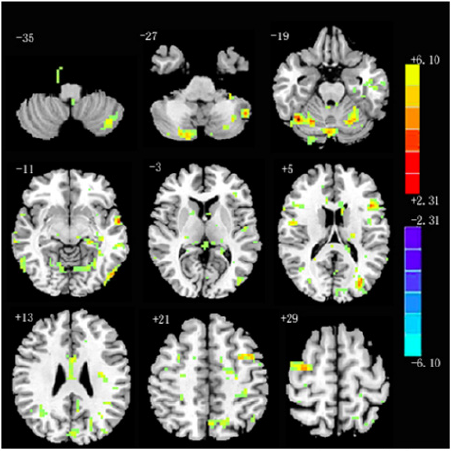

Alff values of bilateral cerebellar hemisphere, bilateral frontotemporal occipital parietal lobe, thalamus and basal ganglia in group A were significantly higher than those in group B (P < 0.05) (Figure 1). Alff values of right temporal lobe in group A1 were significantly higher than those in group A2 (P < 0.05). Alff values of bilateral cerebellar hemisphere, bilateral frontotemporal parietal lobe, left thalamus and basal ganglia in group A1 were significantly lower than those in group A2 (P < 0.05) (Figure 2).

Figure 1:

At present, the pathogenesis of migraine is not clear. At present, the mainstream theories of migraine pathogenesis mainly include trigeminal neurovascular theory and cortical spreading inhibition theory [6]. It is very important to explore the relationship between the changes of migraine brain functional areas and clinical manifestations, so as to achieve effective treatment results and improve the quality of life of migraine patients [7]. In this clinical study, the resting state fMRI technology was used to compare the brain functional activity areas of group A and group B. It was found that there were significant differences in Alff signal values of bilateral cerebellum, bilateral frontotemporal occipital parietal lobe, thalamus and basal ganglia in the case group (group A). The brain dysfunction areas in this study are similar to those in previous studies [8-10], and most of them are related to brain function areas about pain processing, such as frontal lobe, parietal lobe, temporal lobe, cerebellum, basal ganglia, etc. Studies have confirmed that there are lateral and medial pain systems in the brain, and the lateral pain system is responsible for pain recognition; The medial pain related system is responsible for processing the emotional and physical responses to pain. These two pain related systems can be combined into a pain related network, namely “pain matrix”. The pain matrix mainly includes frontal lobe, primary and secondary sensorimotor cortex, Anterior Cingulate Cortex (ACC), thalamus, Insular Cortex (IC), basal ganglia, cerebellum, amygdala, hippocampus, parietal lobe and temporal lobe [8,11]. Repeated migraine attacks can also lead to the reduction of cognitive function [4] and the damage of related brain functional areas, resulting in a vicious circle. This study found that compared with group B, migraine in group a can lead to cognitive dysfunction, specifically in visual space and executive, attention, orientation. In conclusion, according to whether there was patent forman ovale, this study divided migraine patients into different groups, and revealed the abnormal changes of brain functional areas in migraine patients more intuitively by resting state fMRI. At the same time, through the comparison of MOCA score, it revealed that migraine can lead to cognitive dysfunction in patients, manifested in visual space and executive, attention and orientation. Therefore, this study is helpful to explore the pathogenesis of migraine and guide the treatment according to the clinical manifestations.